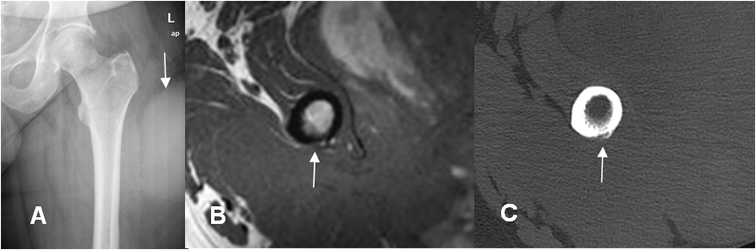

Fig 6. Invasión cortical.

A: Rx AP. No se encuentran anormalidades óseas. Prominencia de los tejidos blandos de predominio en la parte lateral del muslo, por proceso neoplásico.

B: RM axial en T1. Patología neoplásica de crecimiento agresivo y que cruza compartimientos. Se encuentra adelgazamiento en la cortical posterior del fémur, existiendo sospecha de invasión ósea.

C: TAC axial en ventana ósea. Erosión cortical secundaria a compromiso óseo, de un tumor de tejidos blandos.